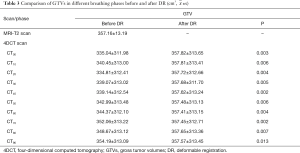

Ten patients (median age 50, range, 38–60 years) with HCC as confirmed by pathology or imaging, were recruited for this study from the Shandong Cancer Hospital between September 2015 and January 2016. The study was approved by the Research Ethics Board of the Shandong Cancer Hospital, with all patients providing written informed consent at enrollment. None of the patients included in the study received TACE. Prior to receiving initial radiotherapy, the patients’ Karnofsky performance status was greater than 80. The patient characteristics are summarized in Table 1.

Full table